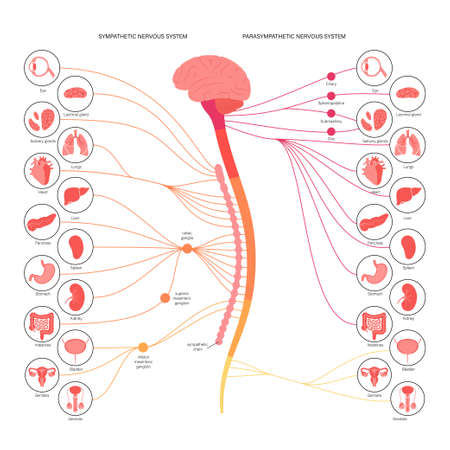

Diagram illustrates the differences between the parasympathetic and sympathetic nervous systems, presented in soothing colors to enhance understanding.

Autonomic nervous system

Human nervous system. Sympathetic and parasympathetic nerves anatomy and functions. Spinal cord controls body internal organs vector diagram